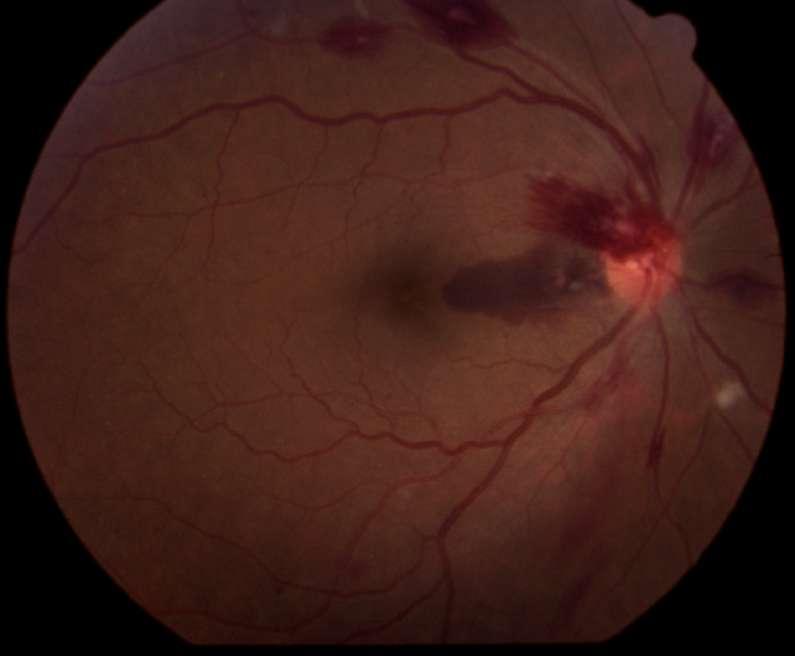

4.A. RETINOPATÍA POR LEUCEMIA MIELOIDE AGUDDA

Imágenes aportadas por Dra. Cavieres

Imagen A y B:

ü Hemorragias en llamas

ü Focos blancos algodonosos

ü Manchas de Roth

ü Las manifestaciones típicas de la leucemia reflejan el cuadro general de anemia o pancitopenia, con hemorragias intrarretinianas e infartos de la capa de fibraas nerviosas (manchas algodonosas). Dentro de las hemorragias tenemos las ”manchas de Roth” que corresponden a hemorragias intrarretineanas con centro blanco

ü En ocasiones puede encontrarse infiltración leucémica de la retina, de la papila óptica o de la coroides, normalmente en la región peripapilar

ü Puede haber compromiso neuroftalmológico como edema de papila por hipertensión intracraneana cuya diferencia con la infiltración directa esta dada por la toma de AV o DPAR

ü En estos paciente siempre se debe descartar compromiso secundario por infecciones oportunistas

Yannuzzi L “Leucemia” Atlas de la retina, editado por Lawrence A Yanuzzi Elservier ediciones 2011 págs 729-736

A B